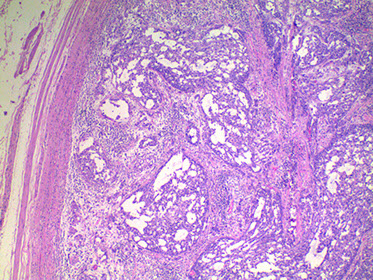

Balanitis Xerotica Obliterans

- aka lichen sclerosus et atrophicus

A chronic progressive sclerosing process of inner foreskin that frequently results in urethral stenosis usually in middle-aged men that could be 2/2 autoimmune dz

Micro: identical to lichen slerosus et atrophicus (red white and blue babyyy!) of vulva, a chronic and atrophic mucocutaneous dz

- thin or thick epidermis with orthokeratotic hyperkeratosis

- vacuolar degen of basal layer, diffuse fibrosis and deep lymph infiltrate